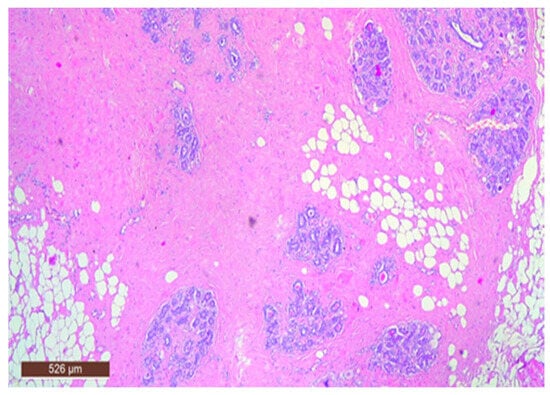

On microscopic examination, a hamartoma may exhibit three predominant components: glandular, fibrous and adipose (Figure 7). Epithelial components such as ducts and lobules are generally normal, featuring a single layer of epithelium overlying the myoepithelial cells. The fibrous component was composed of connective tissue stroma with a delicate connective tissue capsule (Figure 8). Additionally, the ducts within the hamartoma may display apocrine metaplasia (Figure 9).

Figure 7. Hamartoma—histological structure (HE ×40).